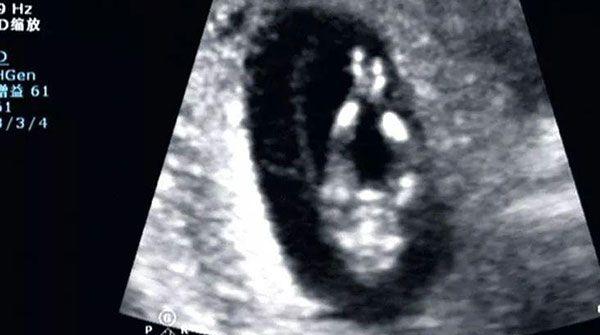

在生育的过程中有这么几次特殊的检查,包括nt检查和唐氏筛查以及无创DNA检查,这些检查的目的都是为了排除胎儿在子宫内染色体发生了异常。当nt值为4.4mm时,表示nt值已经高出正常值不少,此时胎儿存在危险的可能性较大,需要做进一步的检查来确定胎儿是否畸形。

通常我们在nt检查流程完成后,医生都会告知每一项检查指标的作用,而nt检查最重要的意义就是将结果和正常的nt范围值进行对比,如果数值偏高,表示胎儿畸形的可能性较大,当为4.4mm时,已经远远超过其正常临界值,所以此时胎儿的处境是很危险的。